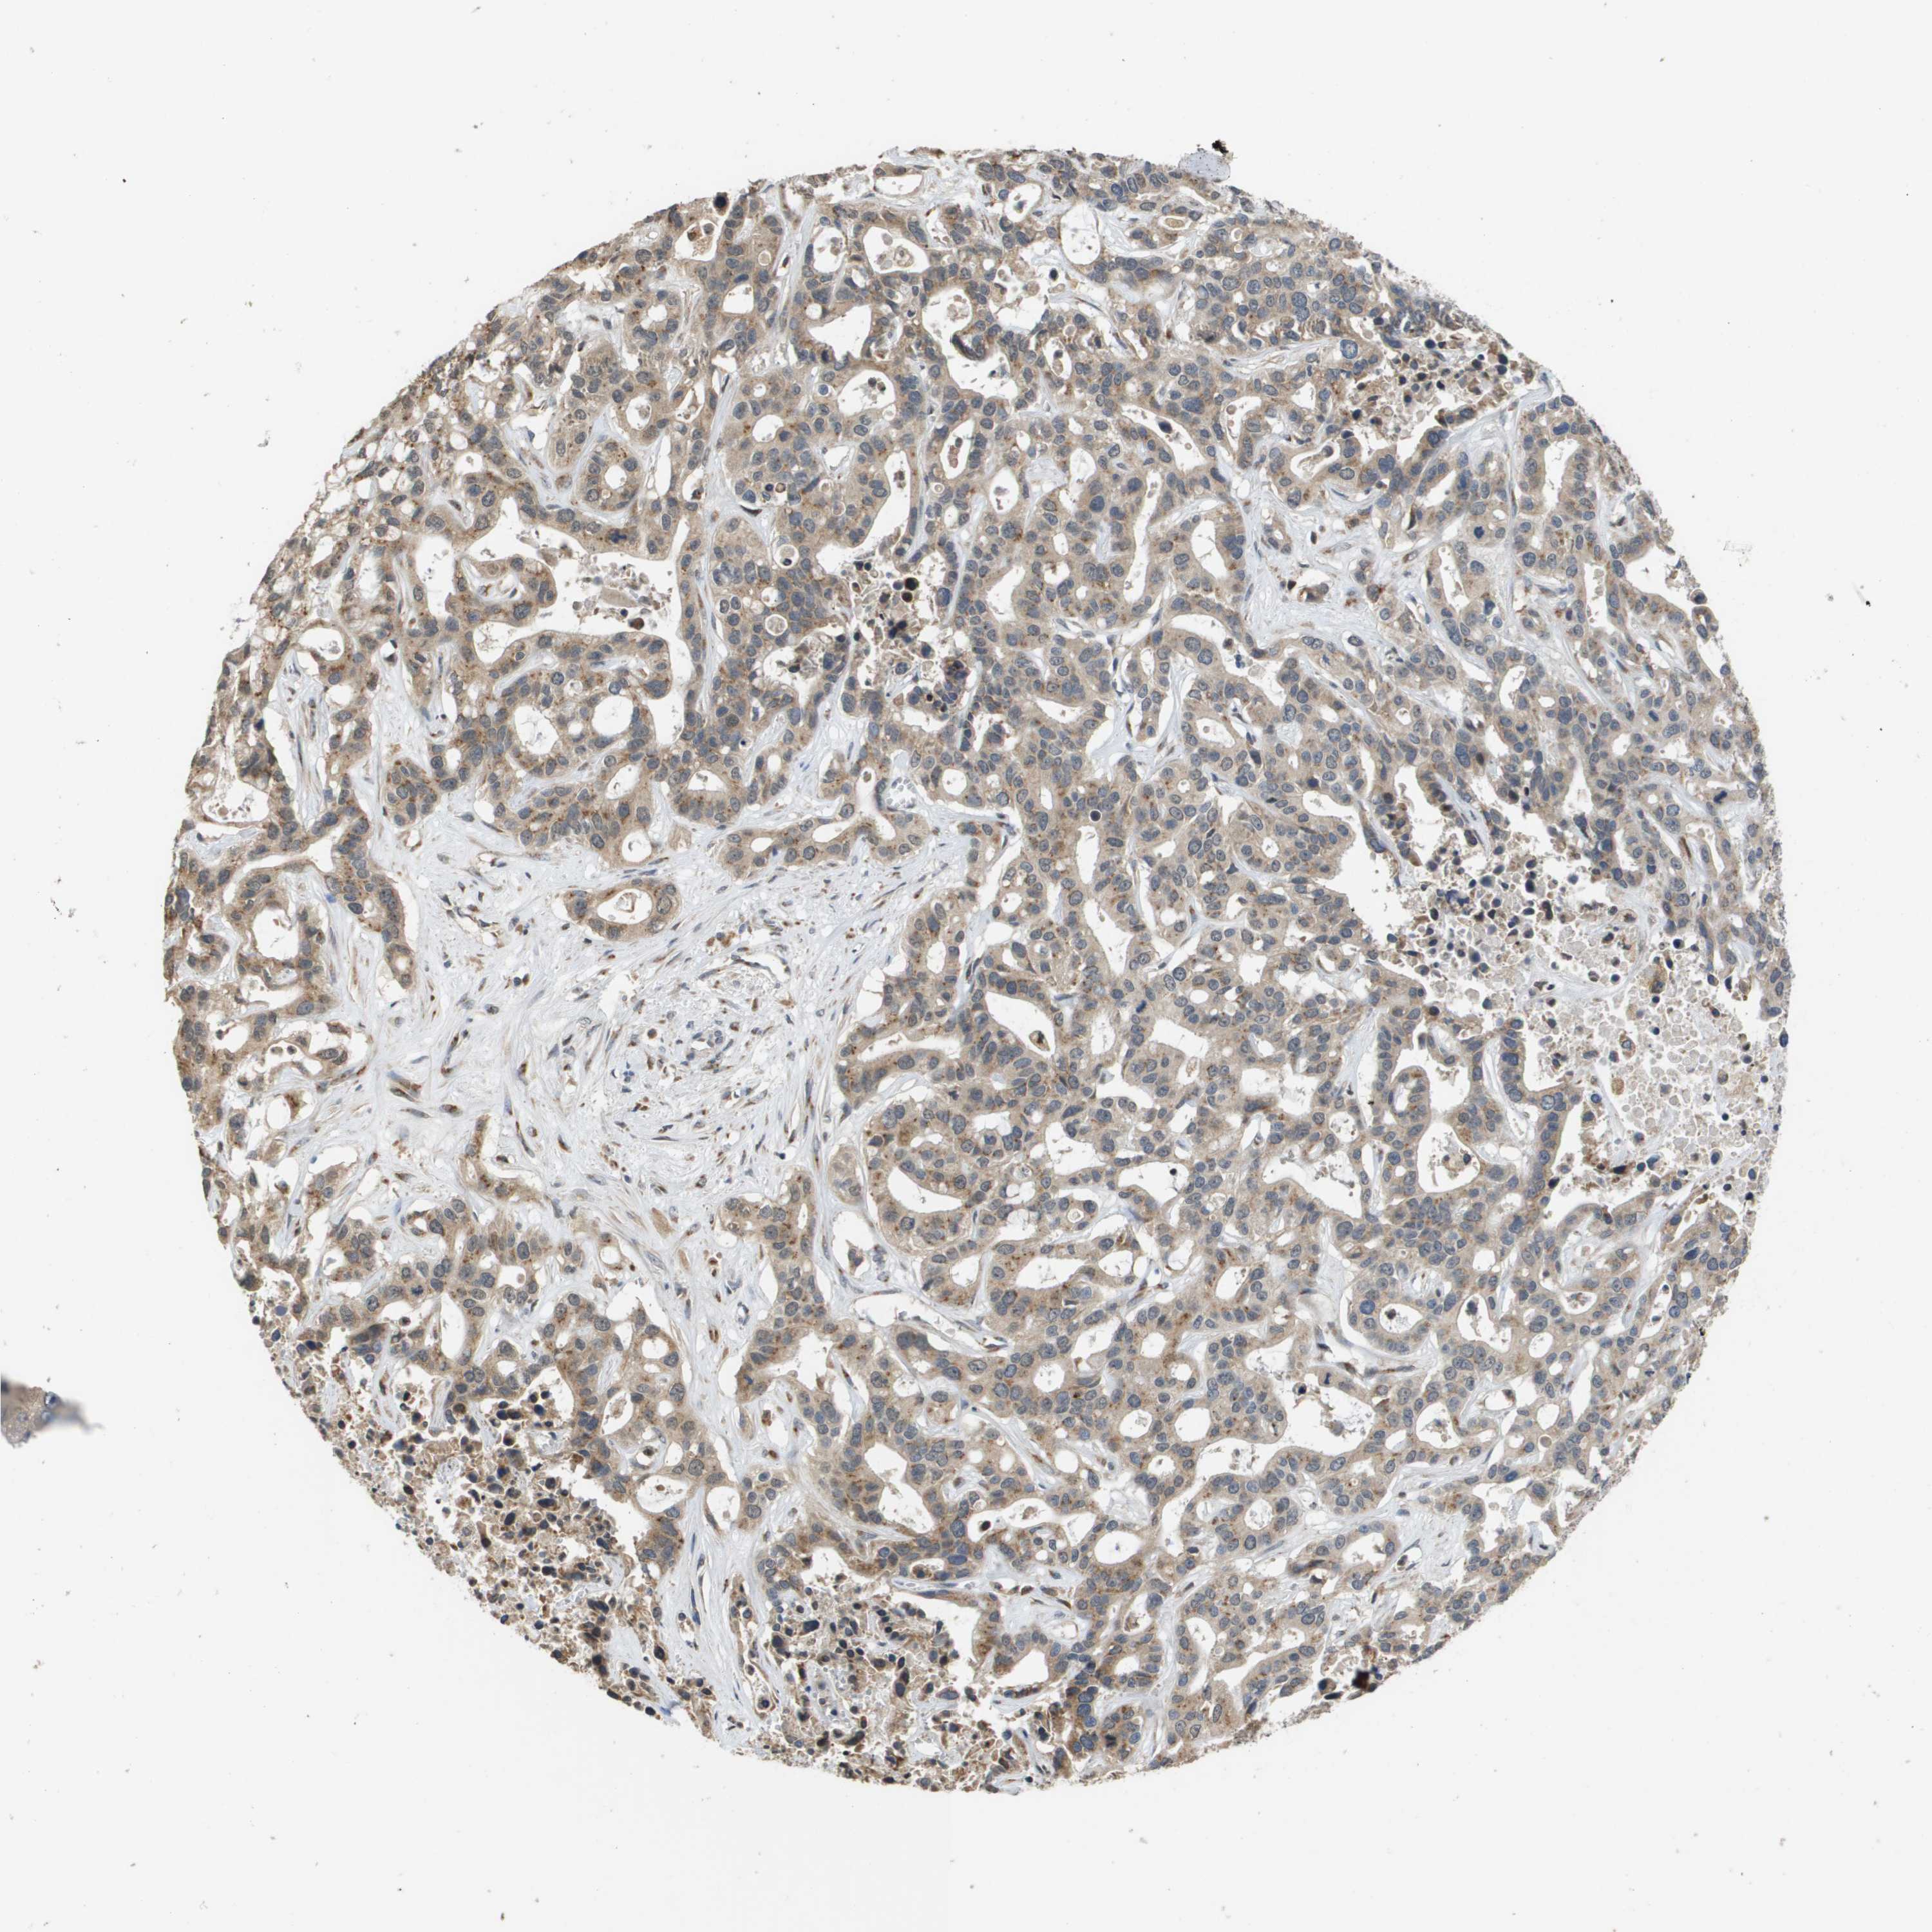

LIVER CANCER - Protein expressioni

A mouse-over function shows sample information and annotation data. Click on an image to view it in a full screen mode. Samples can be filtered based on level of antibody staining by selecting one or several of the following categories: high, medium, low and not detected. The assay and annotation is described here.

Note that samples used for immunohistochemistry by the Human Protein Atlas do not correspond to samples in the TCGA dataset.

Antibody stainingi

Antibody staining in the annotated cell types in the current human tissue is reported as not detected, low, medium, or high, based on conventional immunohistochemistry profiling in selected tissues. This score is based on the combination of the staining intensity and fraction of stained cells.

Each image is clickable and will lead to virtual microscopy that enables deeper exploration of all samples and also displays staining intensity scores, fraction scores and subcellular localization as well as patient and tissue information for each sample.

Antibody HPA006277

Antibody HPA006507

Antibody CAB017027

Staining

High

Medium

Low

Not detected

Intensity

Strong

Moderate

Weak

Negative

Quantity

>75%

75%-25%

<25%

None

Location

Nuclear

Cytoplasmic/membranous

Cytoplasmic/membranous,nuclear

Cholangiocarcinoma

Carcinoma, Hepatocellular, NOS